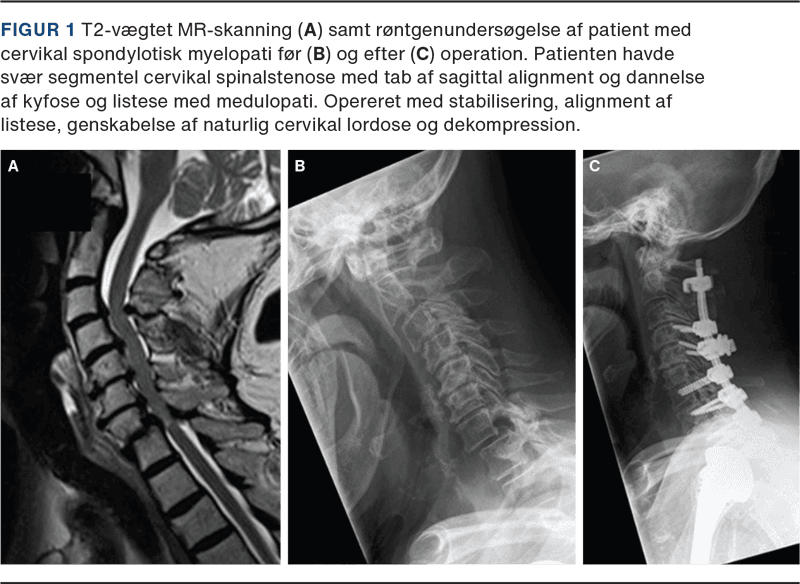

Cervikal spondylotisk myelopati (CSM) er en hyppigt forekommende progressiv tilstand, der er kendetegnet ved aldersrelaterede degenerative forandringer i columna cervicalis, hvilket resulterer i gradvist ophævet liquorflow og efterfølgende kompression af rygmarven og/eller de omgivende blodkar [1, 2]. Kompressionen opstår med baggrund i den spondylotiske ryg med degenerative forandringer omkring diskus, vertebra, facetled og ligamenter medførende nedsat plads i spinalkanalen (Figur 1) [2, 3].

MR-skanning af columna cervicalis er den foretrukne billedmodalitet og et uundværligt redskab i udredningen af CSM (Figur 3). Ved konventionel MR (T1/T2/STIR-vægtet) kan klinikeren verificere graden af degeneration (spondylose, ossifikation af posterior longitudinale ligament, diskusprolaps, hypertrofi af lig. flavum, osteofytdannelse), rygmarvskompression, ændringer i spinalkanalens diameter og ændringer i signalintensiteten (Figur 1) [2, 22, 23]. Bl.a. kan signalændringer i rygmarven have en prognostisk betydning for patienten. På T2-vægtet optagelse vil en lav signalintensitet uden skarp afgrænsning generelt repræsentere potentielt reversibel myelopati. Derimod vil høj signalintensitet på T2- og lav signalintensitet på T1-vægtede billeder ofte repræsentere irreversibel myelopati såsom kavitation, neuralt vævstab, myelomalaci, nekrose og spongiforme ændringer i den grå substans [14, 18, 22, 23]. Herudover er MR nødvendig for at udelukke differentialdiagnoser til CSM såsom tumor, syringomyeli, demyeliniserede plaques mv. (Figur 3). Det er vigtigt at understrege, at MR-skanningens fund ikke kan stå alene, da det ikke er ualmindeligt, at asymptomatiske patienter har billeddiagnostiske tegn på CSM [9, 23, 24].